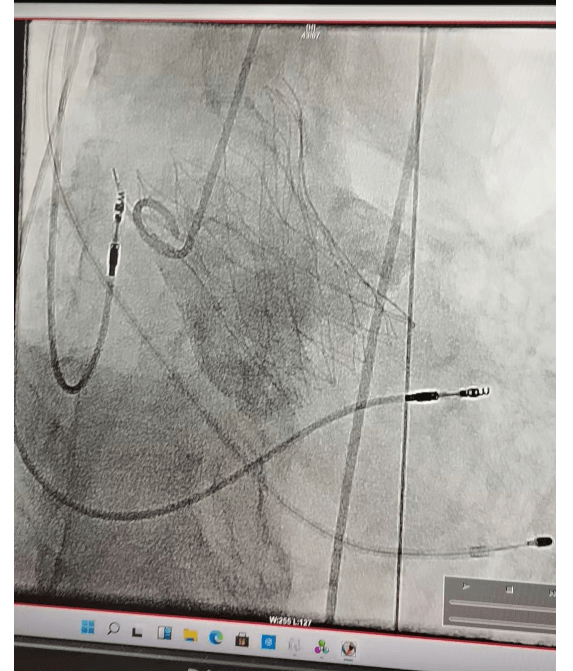

4月11日在全麻下行经皮介入下主动脉瓣置换术。经右侧股动脉,在DSA引导下经传输器将人工主动脉瓣膜送入主动脉瓣环内,定位准确后逐步释放人工瓣膜,完成瓣膜置换,术后超声显示人工瓣膜固定良好,无瓣周漏,无返流。手术历经约两小时顺利结束,超声显示,主动脉瓣跨瓣压差基本消失,返流大大减轻。手术获得成功,术后患者24小时下床活动,恢复良好出院!